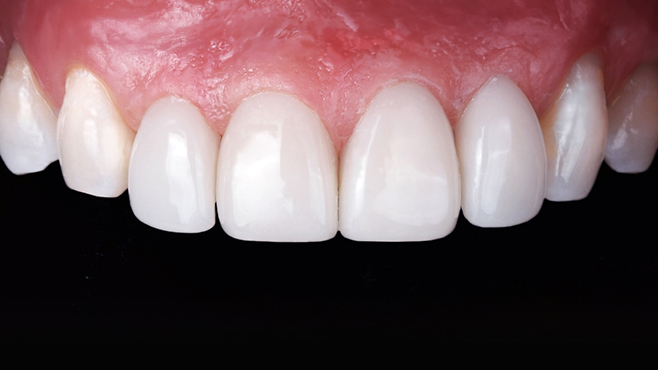

맞는 건 괜찮은데… 충치는 못 참겠습니다|20대 격투기 선수 치과 방문기